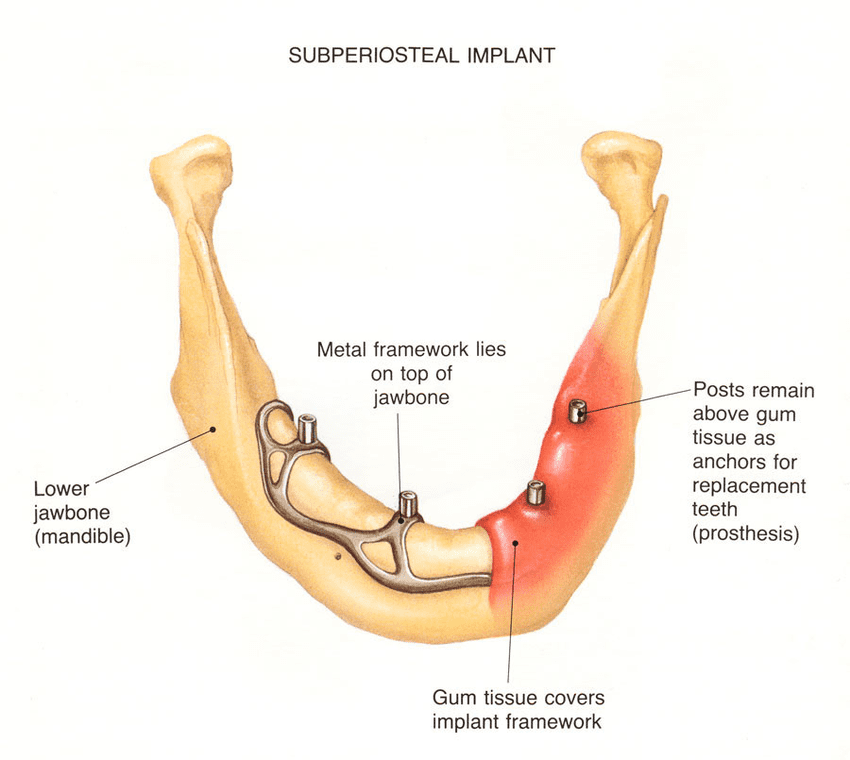

2. Sub-periosteal Implants:

Sub-periosteal implants are an alternative to endosteal implants for patients who have insufficient bone height or density in their jawbones. Instead of being placed inside the jawbone, sub-periosteal implants are positioned on top of the bone and beneath the gum tissue. A metal framework is used to support the prosthetic teeth, which are attached to the implants. Sub-periosteal implants are often recommended for patients who cannot undergo bone grafting procedures or who prefer a less invasive option.